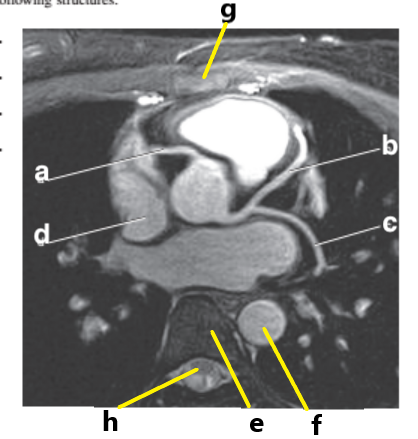

What is letter a ?

Left Ventricle

Left atrium

Right ventricle

What is letter h ?

What is letter d ?

What is letter g ?

Right atrium

What is letter b ?

Pulmonary trunk